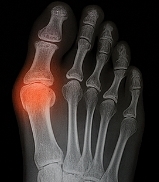

통풍 증상 중 가장 대표적인 것은 관절 부위의 극심한 통증과 붓기입니다. 대개 밤이나 새벽에 갑자기 찾아오며, 통증이 너무 심해 이불이 닿기만 해도 견디기 힘든 수준입니다. 통풍 증상은 주로 엄지발가락에서 시작하지만, 발목·무릎·손가락 등 다른 관절로도 퍼질 수 있습니다. 초기에는 2~3일 후 통증이 가라앉지만, 재발을 반복할수록 통증 기간이 길어지고 염증이 심해집니다.

② 관절 부위의 열감 및 홍조

통풍 증상에서는 통증뿐 아니라 열감과 붉은 피부색 변화가 동반됩니다. 염증이 심해지면 해당 부위의 온도가 올라가고, 손으로 만지면 뜨겁게 느껴집니다. 통풍 증상은 염증 반응이 활발할 때 발목, 발등, 손가락 관절 등이 붉고 붓는 양상으로 나타납니다.

4. 영상 검사 (X-ray, 초음파, CT)

관절 변형, 토피(요산 결절), 염증 범위를 평가하기 위해 시행됩니다. 초음파에서는 관절 주변의 미세한 요산 침착도 확인 가능하며, CT는 장기적 손상 여부를 정밀하게 파악할 수 있습니다.